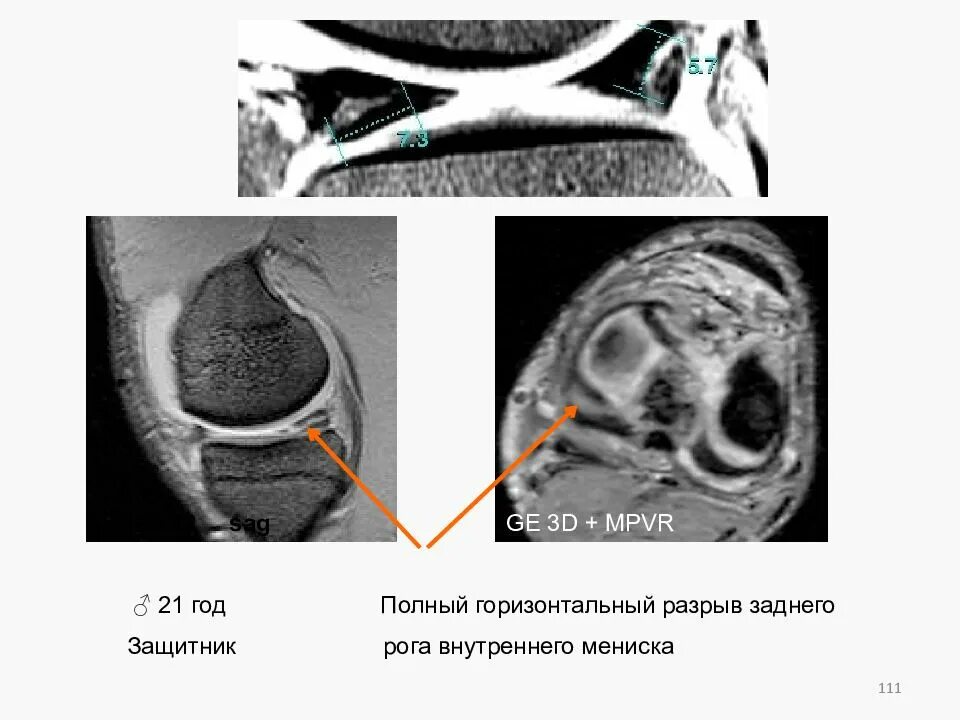

Разрыв заднего